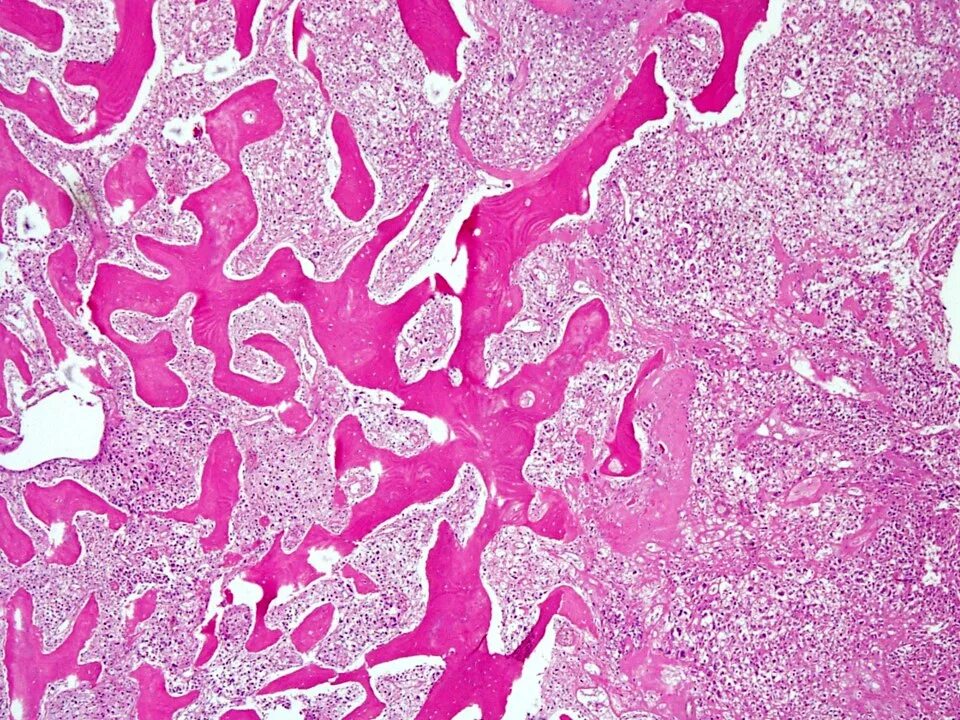

Гистология челюстей